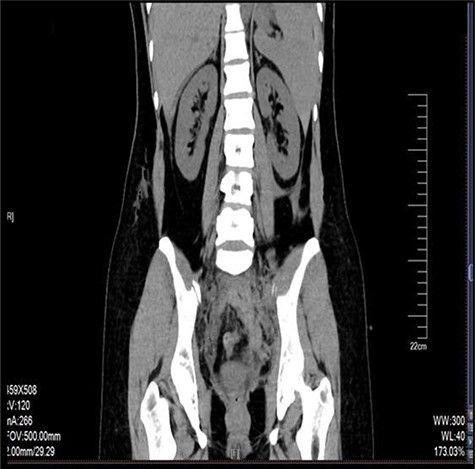

The retroperitoneal hematoma appeared stable and no expanding, also no increase in tension. The hemoglobin concentration reexamination showed no significant change. Considering the bleeding has stopped, the trauma surgeon recommended no further incision for the retroperitoneal hematoma after consultation. Digital subtraction angiography (DSA) was done after operation to further confirm no more artery bleeding. DSA revealed the inferior mesenteric artery and the iliac artery were intact (Figs 2 and 3). The patient was placed in the intensive care unit with a angiographic catheter retained for emergency use. They estimated the total blood loss 1500-2000 ml, 200 ml of fresh frozen plasma and 4 units of packed red blood cells were transfused during operation.

The left iliac artery and inferior mesenteric artery was intact by fluorescence angiography.